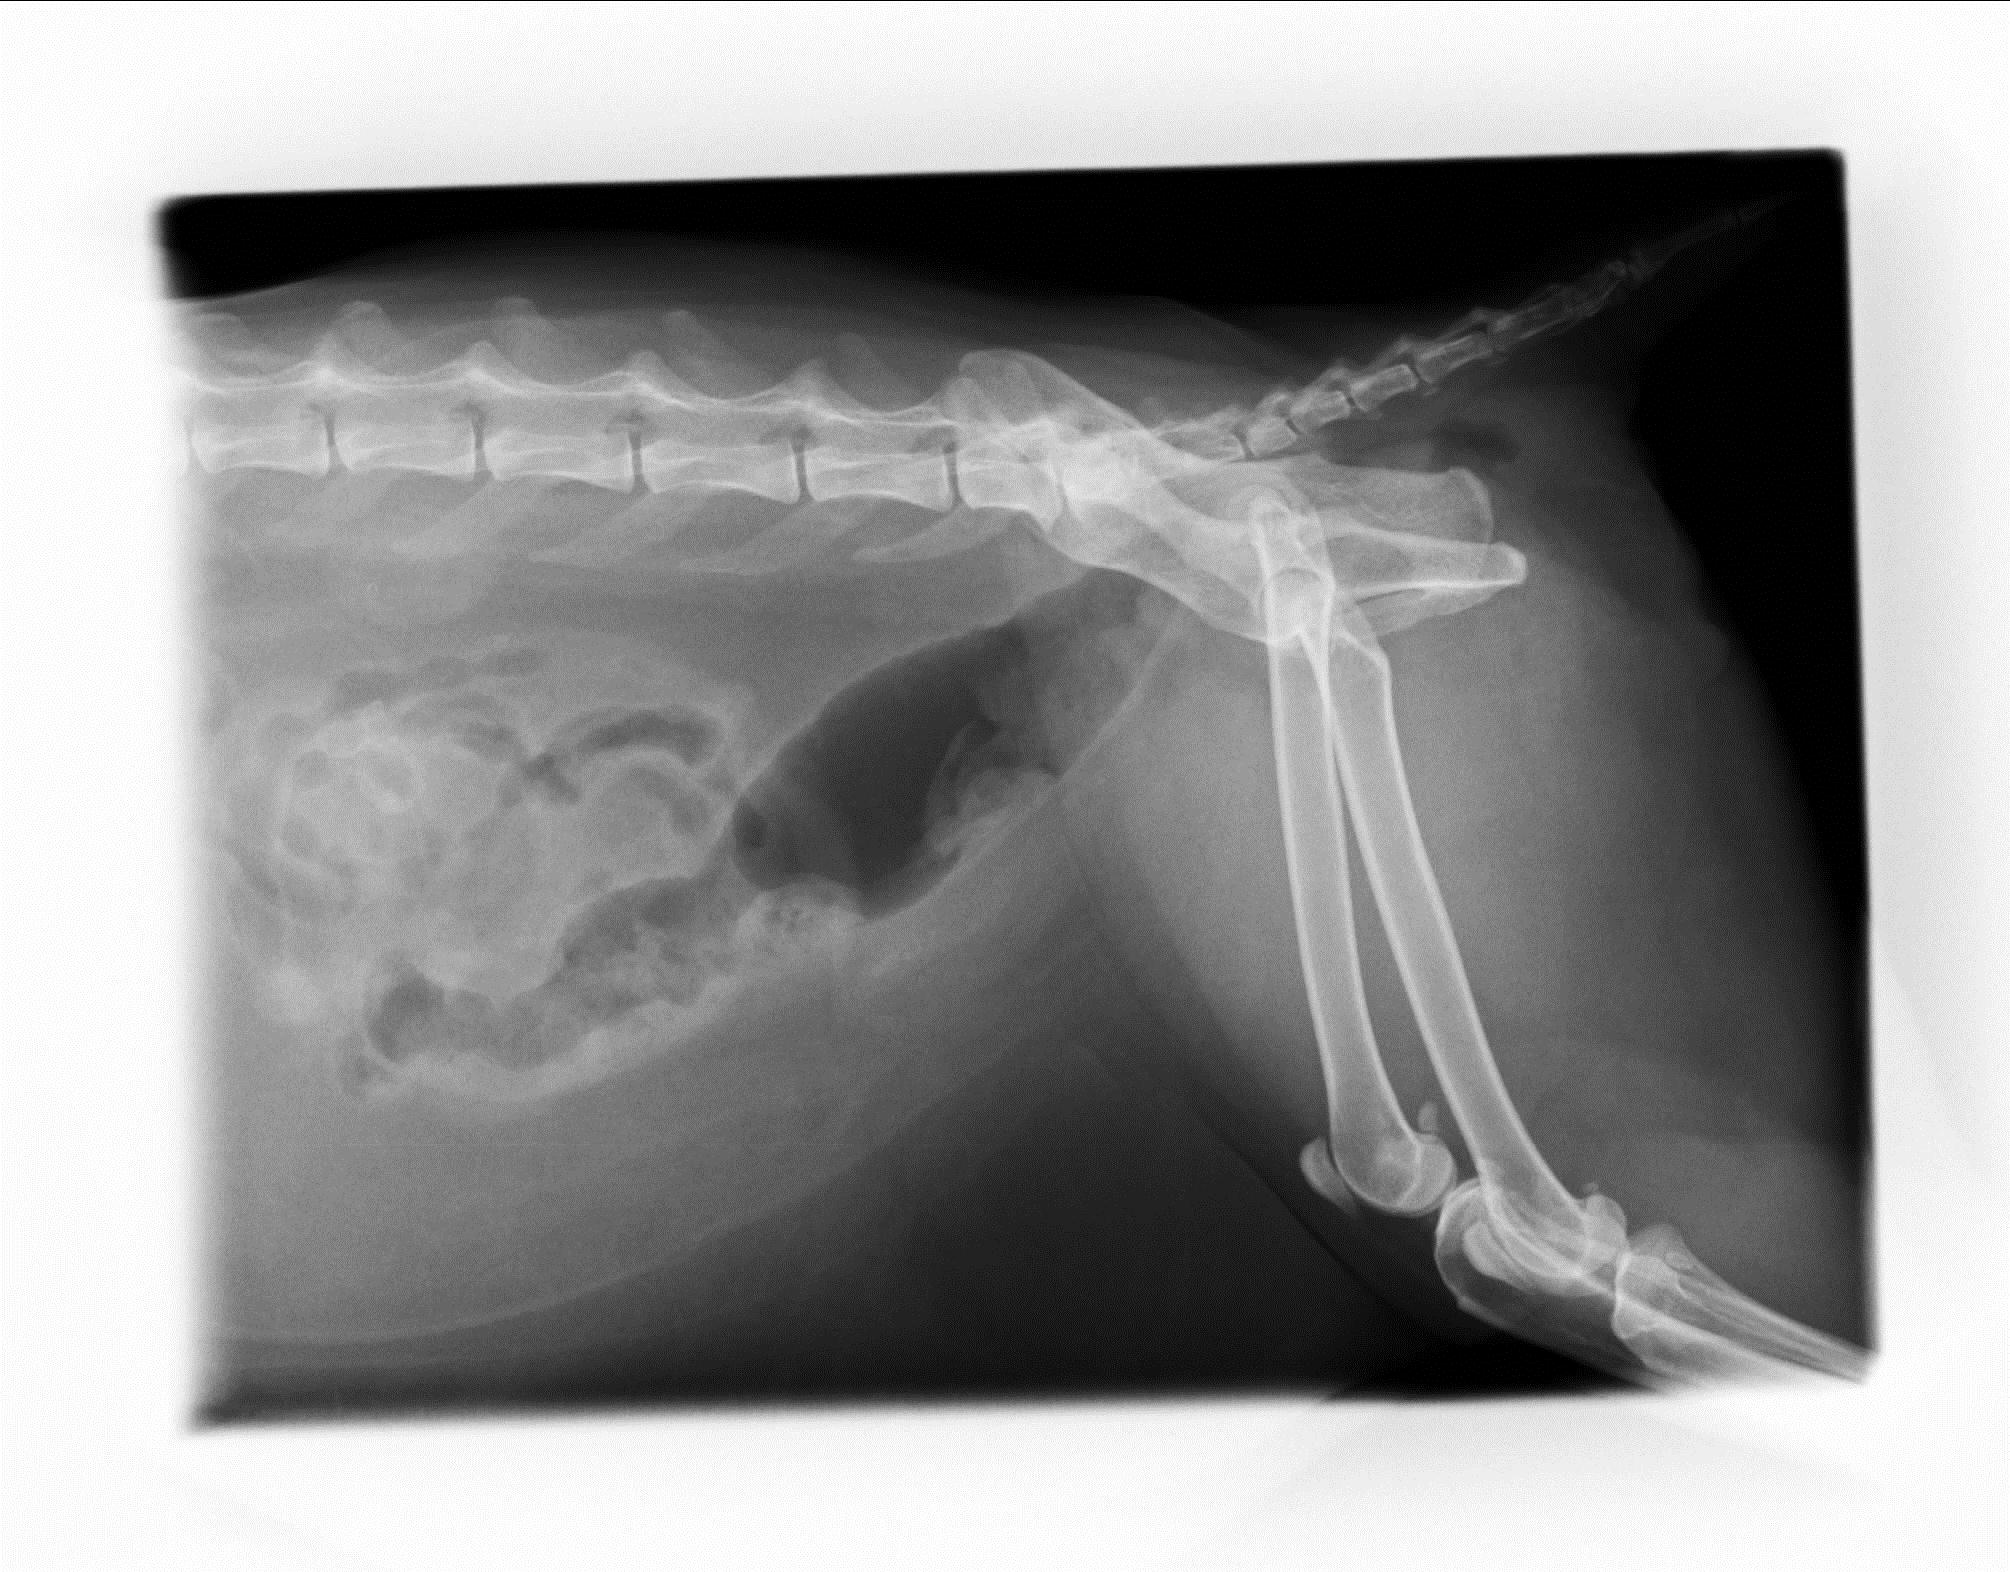

来院時のレントゲン写真 大腸いっぱいに便がつまってます!